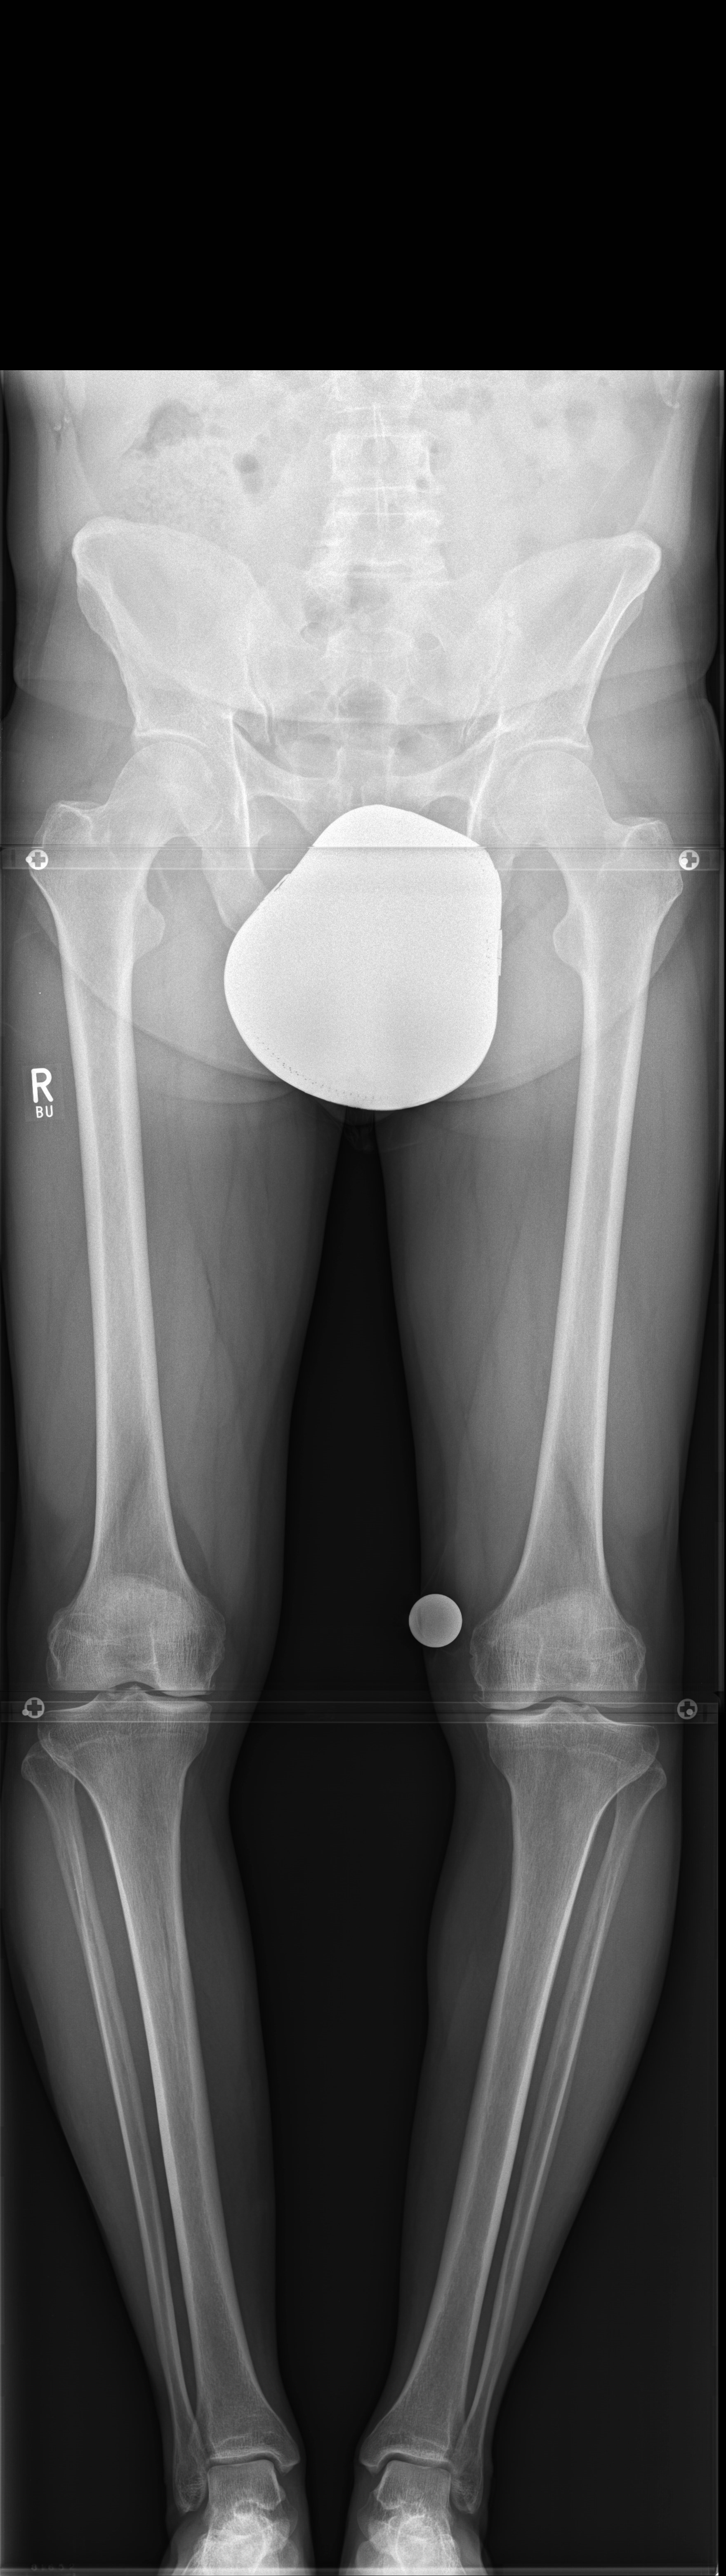

A 33-year-old woman complained of pain in the lateral compartment after a normal working day. Sports activities were no longer possible. Free range of motion (ROM: 0/0/150°), ligaments in sagittal, and coronal planes were stable. There was no effusion. The patient had valgus deformity which was corrected with a distal femoral osteotomy.

Showcasing a distal femur osteotomy case